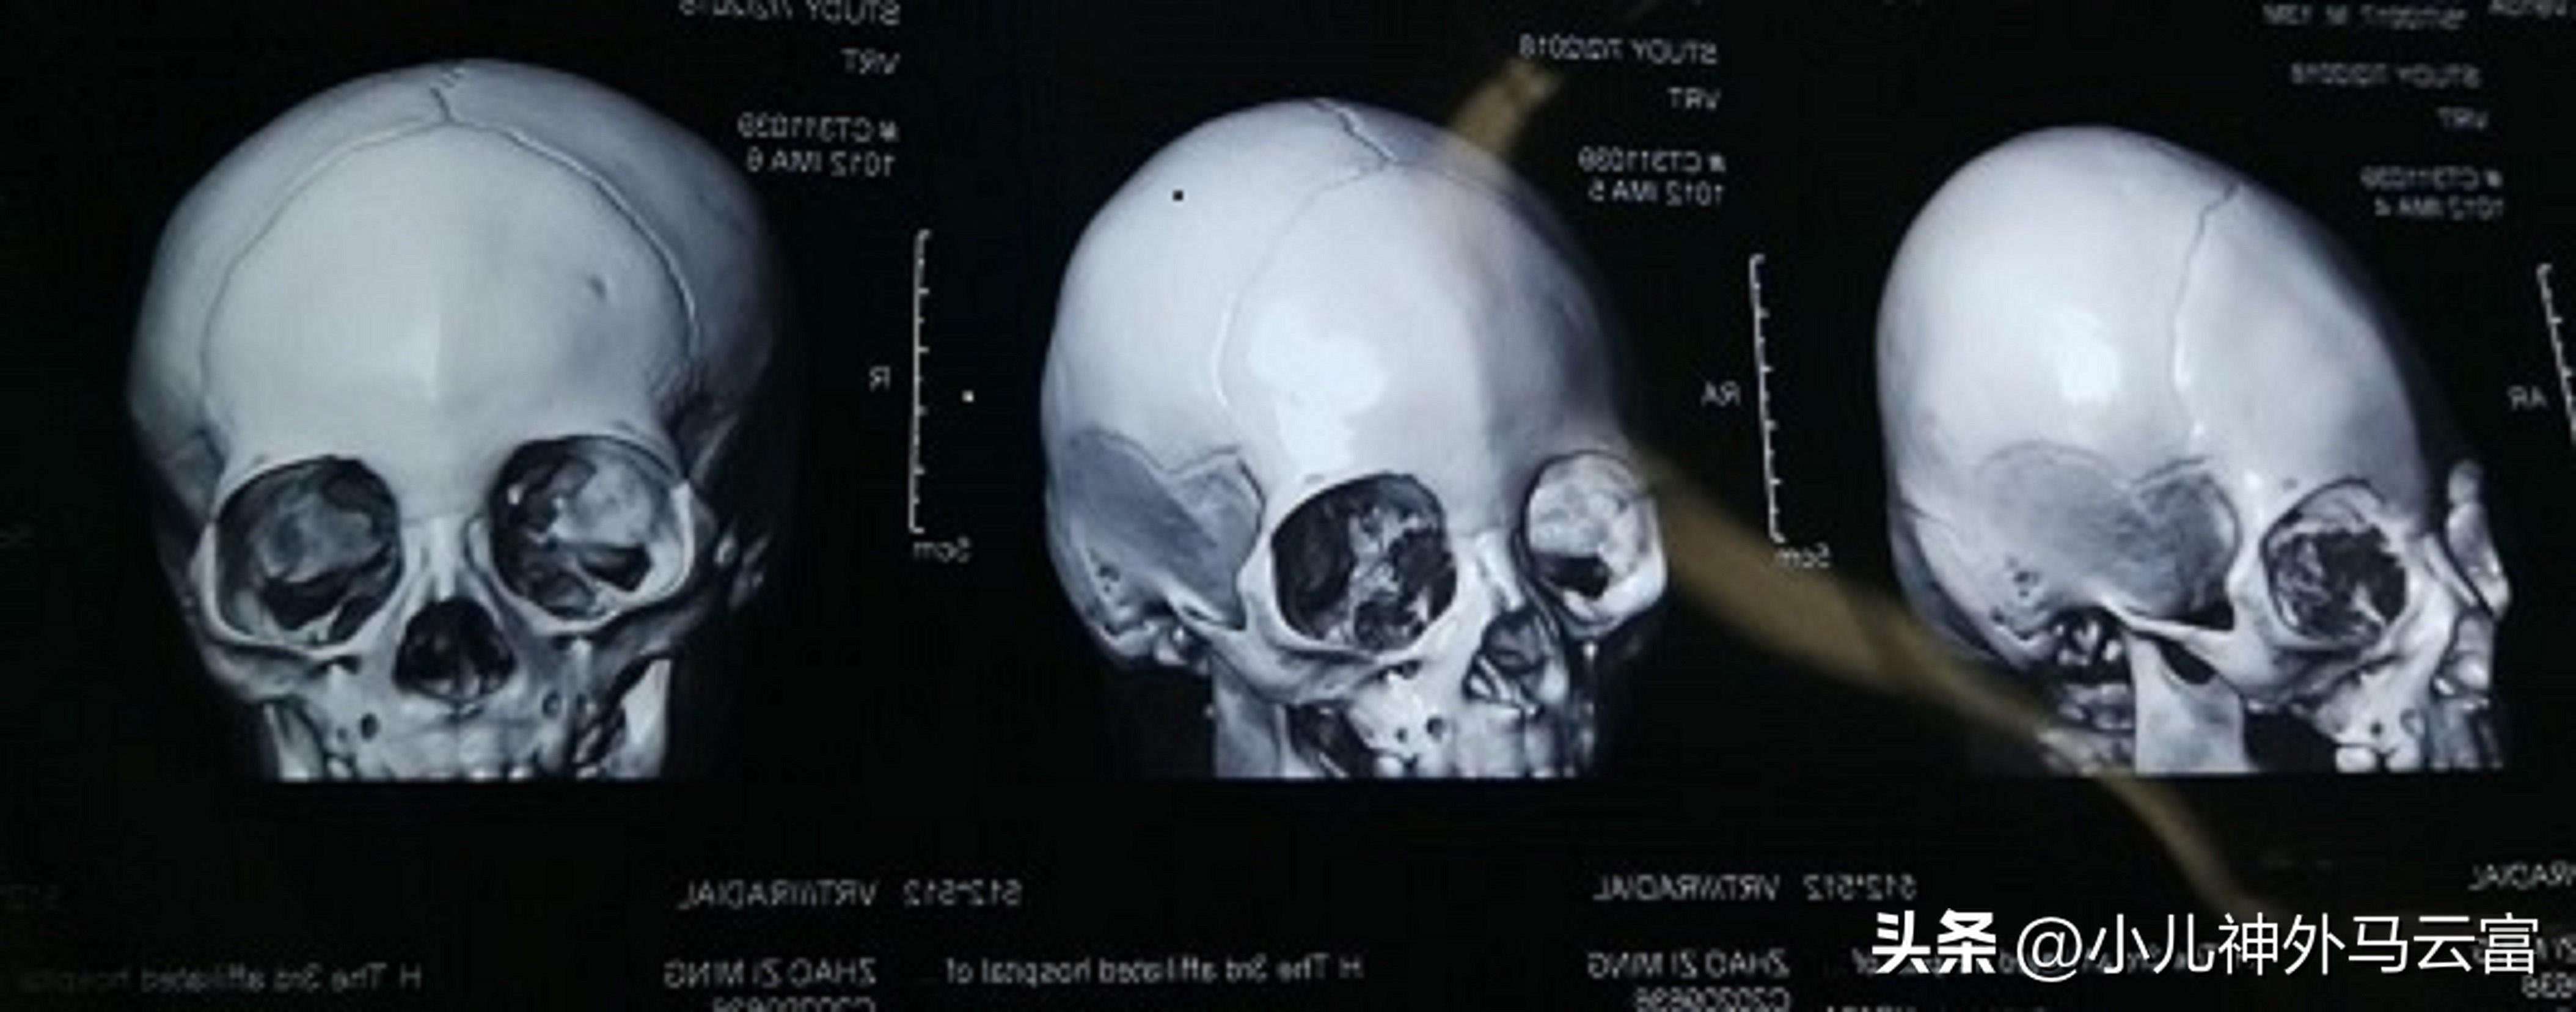

治療小頭畸形前首先應經過頭顱照片及CT等檢查,然後根據患兒的情況設計治療方案。對於有顱內壓升高者,一般建議應儘早進行手術。而對於單純骨縫閉合過早的患兒,可採用神經外科手術療法,能取得一定的療效。通常來說,小頭畸形伴有顱內壓升高者大多以手術治療爲主,目的就是要擴大顱腔,解除顱內高壓,從而使受壓的腦組織及顱神經得到發育和生長。

小頭畸形的伴有顱內壓升高者手術治療一般有兩種方式,一種切除過早閉合的骨縫,再選新的骨縫。另一種就是切除大塊骨質以達到減壓和有利於腦的發育。醫生大多都會建議手術要越早越好,出生後診斷爲小頭畸形的患者在六個月以內手術者術後恢復的較好。如果患兒一旦出視神經萎縮和智能障礙,這時候即使馬上進行手術治療,其大腦功能也已經受損,不易恢復。但是對於腦組織發育較差,顱內壓不高、有明顯萎縮的小頭畸形不適合做此類手術

開展的顱縫早閉、狹顱症手術治療在我省處於領先地位,年手術量150臺左右,根據不同的顱縫早閉類型採取不同方法治療狹顱症,爲衆多頭顱畸形、狹顱症、顱縫早閉患兒帶來了福音。